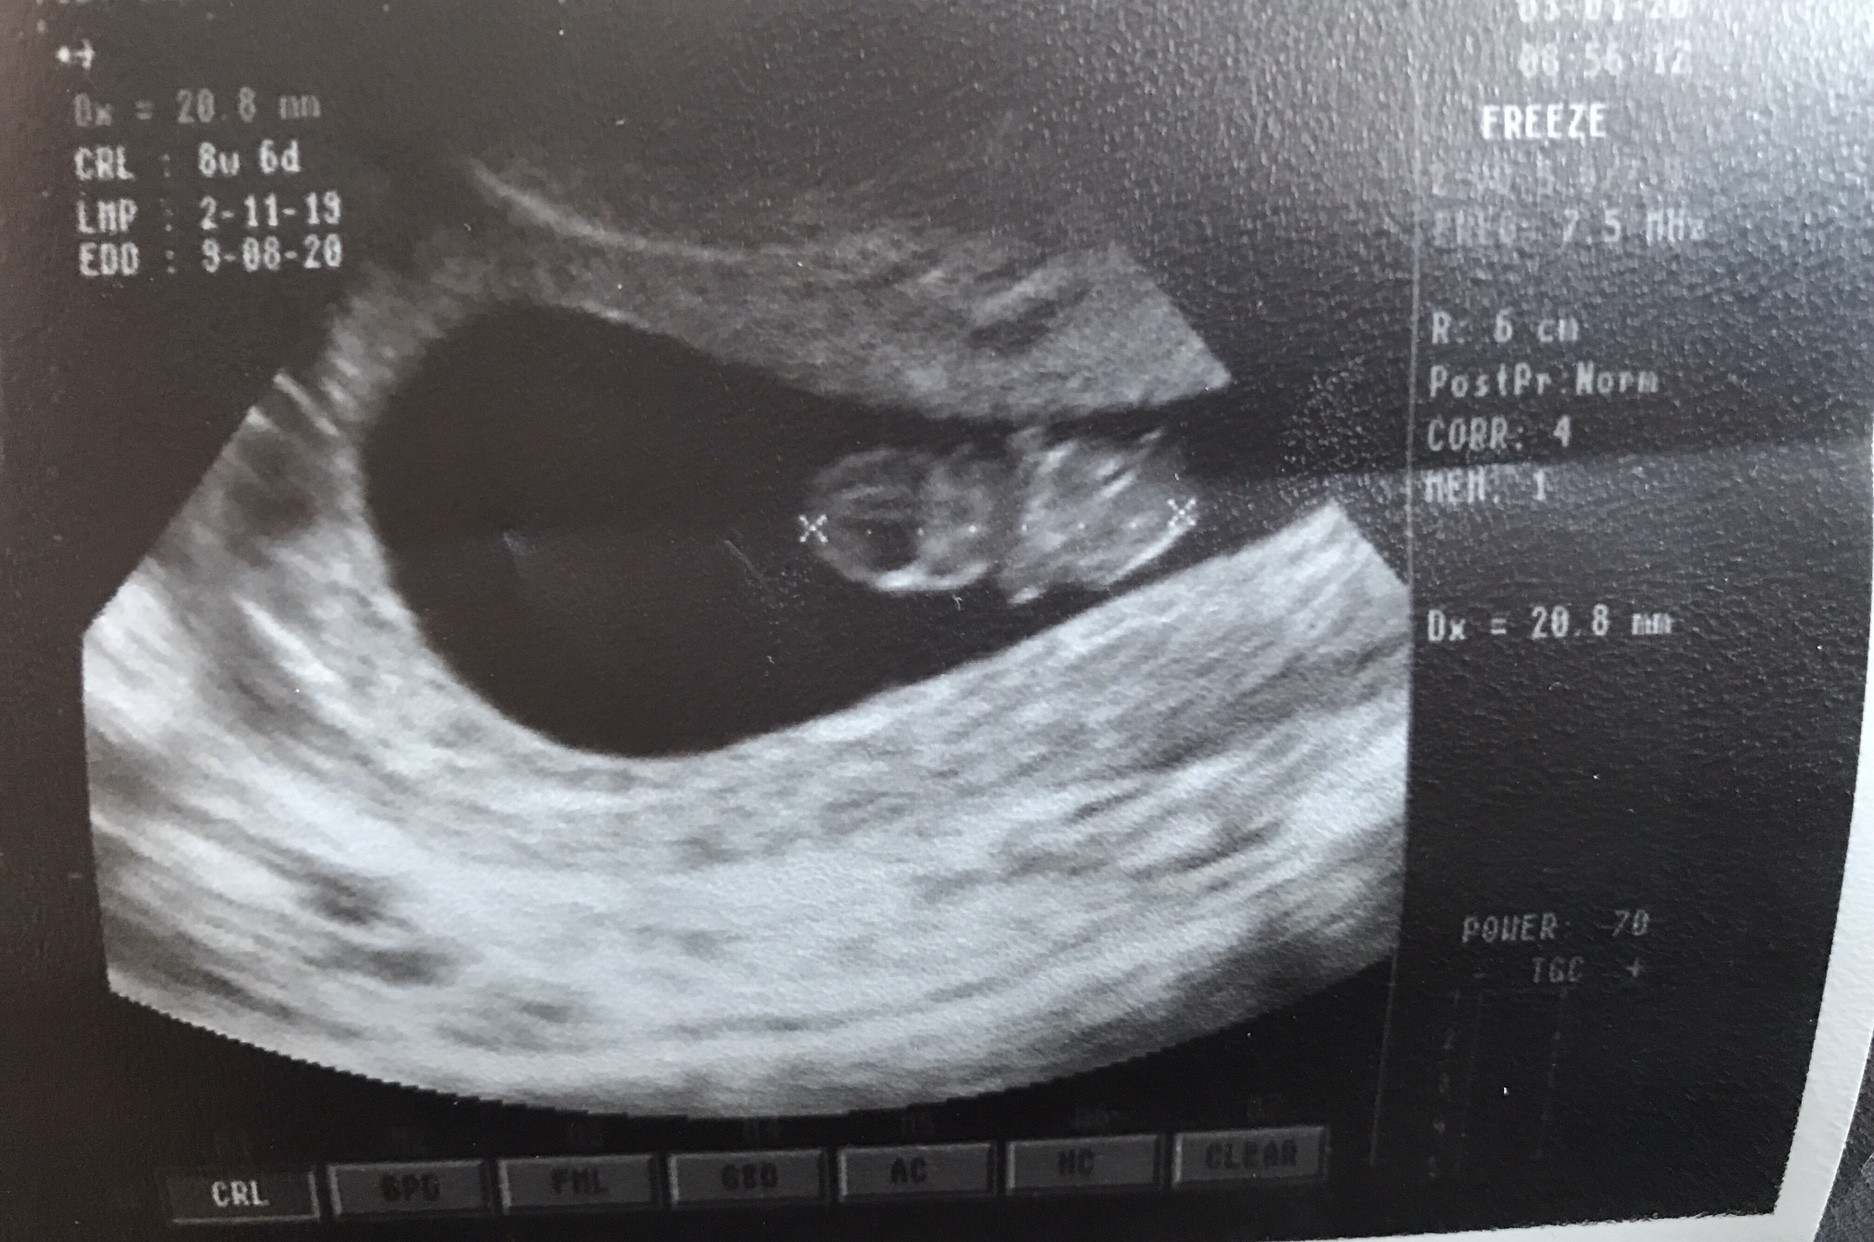

Dolegliwości przeszły mi jak ręką odjął w sylwestra. Tak dobrze się czułam, że wrocilam po 5 do domu [emoji85][emoji4] Teraz tez jest wszystko okej i mam nadzieje, że tak zostanie. Dziś miałam wizytę USG tu u mamy w mieście (lekarz masakra, sprzęt chyba jakiś zabytkowy) i na szczescie wszystko dobrze [emoji4] Fasolinka już ponad 2 cm [emoji1320] Wkleję zdjęcie. A i umówiłam już badanie prenatalne na 28 stycznia [emoji4]

Zobacz załącznik 1063849